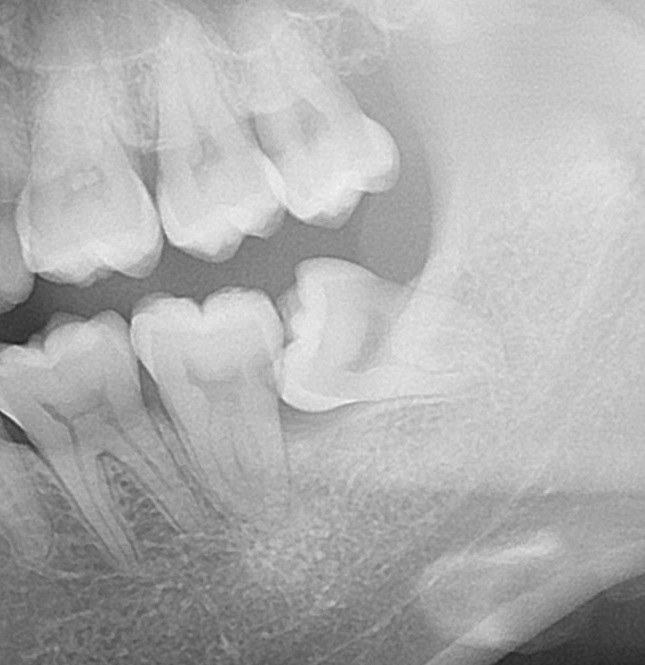

お口の中を見てみると

親知らずが横向きに生えているのが分かります。

左下奥歯の状態です。

よく見ると、手前の歯にぶつかっている親知らずですが、

黒く虫歯になっているのが分かります。

方向が違う歯と歯の間は隙間になるので、汚れが溜まるのが特徴です。